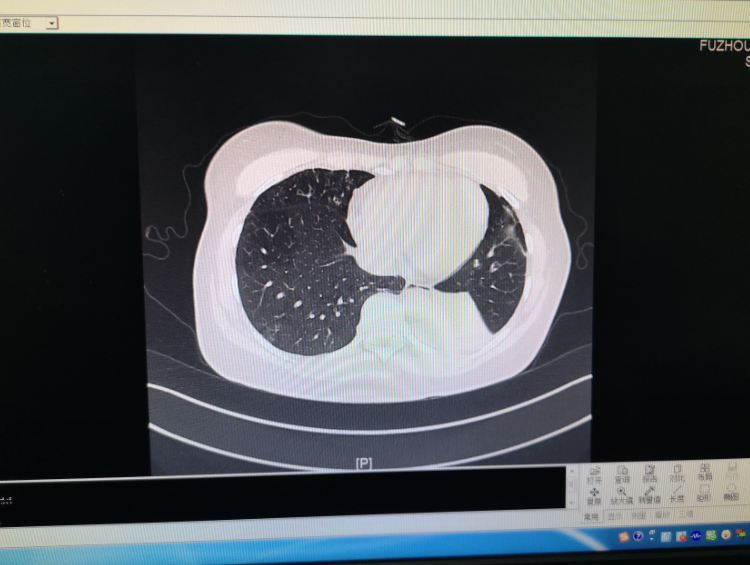

近日,福建省福州肺科医院接诊一名患者,该女子咳嗽两个月未愈,经查确诊为侵袭性支气管肺曲霉菌病。医生表示,内镜检查时,发现患者肺部有非常严重的痰栓及坏死物,已经堵塞管腔,将坏死物活检后去做病理检查,发现了大量的霉菌。

专家表示,霉菌会依附在气管上,稍不注意就会造成气管黏膜的大出血。霉菌全年都有可能感染,尤其在天气潮湿的时候,特别容易生长。目前,该女子通过抗霉菌治疗,情况日渐好转。